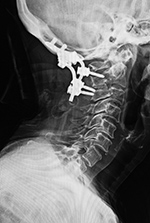

| 68 year-old woman with posterior spinal fixation extending from the occiput to C3 involving posterior elements of C2 and C3 (left image). The surgery was performed for unstable atlantoaxial subluxation after remote cervical spine trauma. CT imaging follow-up (right image) demonstrated the C2 and C3 fixation screws were posteriorly displaced into the spinal musculature. |